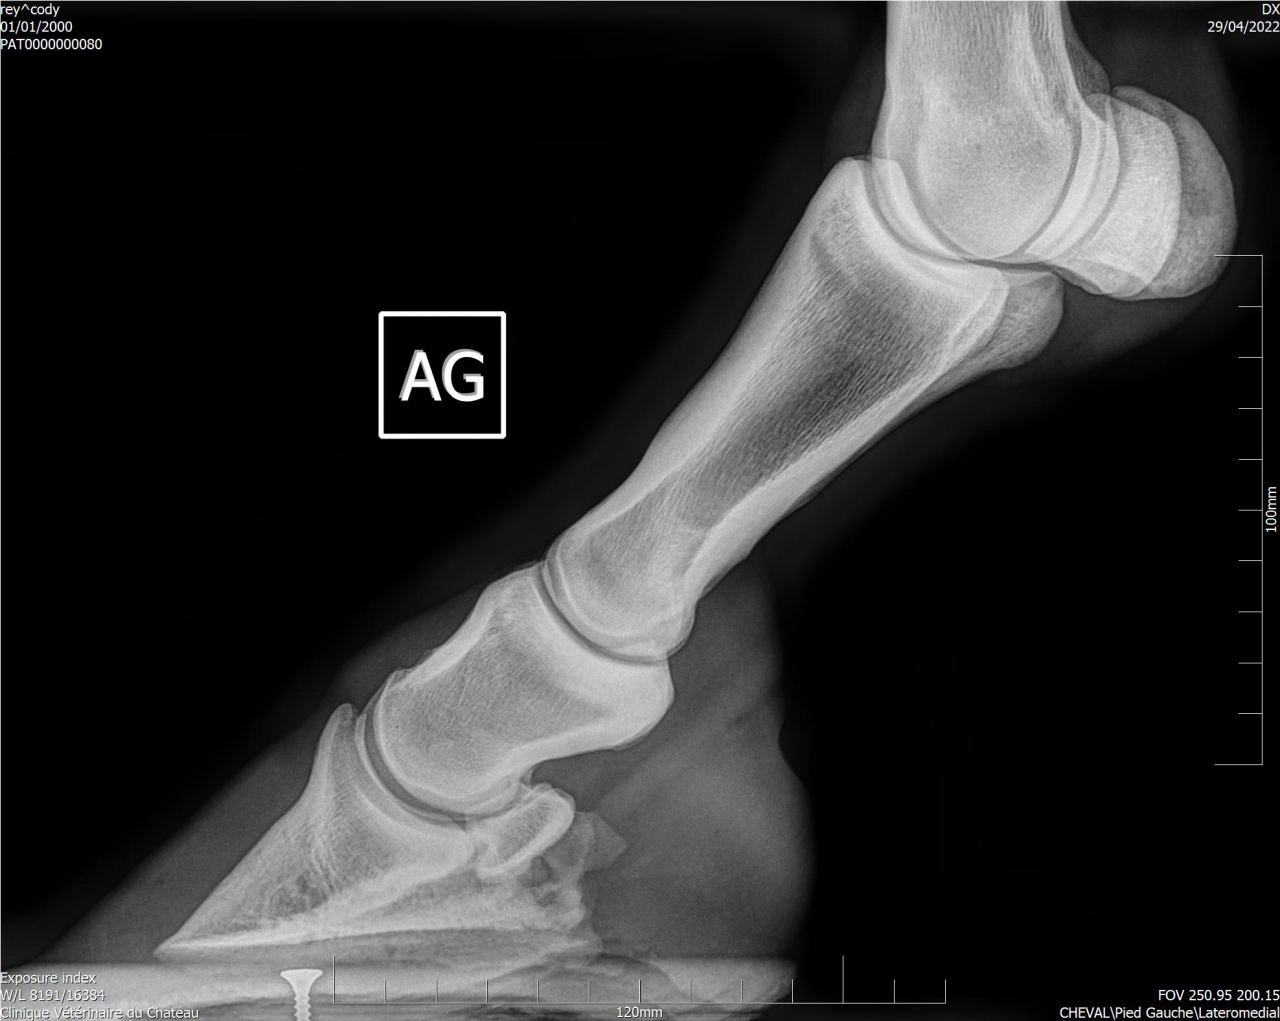

| Dire merci | Je remonte le post Mon cheval a été diagnostiqué naviculaire, il y a des fossettes synoviales. Ma véto préconise une infiltration avec du Tildren ou de l’Osphos. Aujourd'hui mon cheval a été ferré : antérieurs avec oignons et plaques en cuir, ferrure normale aux postérieurs. Voici les radios : ![]() ![]() ![]() ![]() ![]() |

| Dire merci | Les radios LM montrent une pince trop longue et pas de roll/ breakover Agir sur cela soulagera déjà énormément l’arrière du pied ! Sur la dp 60 on voit une zone noire circulaire Aurais tu une photos vue solaire stp ? Y a t’il fourmilière/évasement important voire un abcès récent ? |

| Dire merci | Je n'ai que ça comme radios ... Il y a des fourmilières aux 2 antérieurs. |